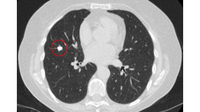

Tomografia computadorizada (TC) mostrando um pequeno nódulo no lobo superior esquerdo com margens lisas, posteriormente considerado uma metástase colorretal solitária na ressecção

Do acervo de Dr. George Tsaknis, MD, PhD, FRCP (Londres), MRQA, MAcadMEd, PGCert; usado com permissão